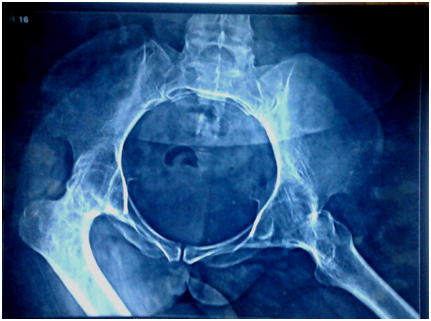

Further investigations included blood workup including inflammatory markers ESR and CRP which were normal, suggesting inactivity of the disease. Radiographs of the knee and hip joints showed bony ankylosis (Figures 2-4) with arthritis of ankle, wrist and shoulder joints and generalized osteopenia. As a part of preanaesthetic checkup chest x-ray and echocardiogram were done and found to be normal.

Figure 2 Radiograph showing bony ankylosis in flexion of both hip joint along with adduction deformity of right and abduction deformity of left hip joint.